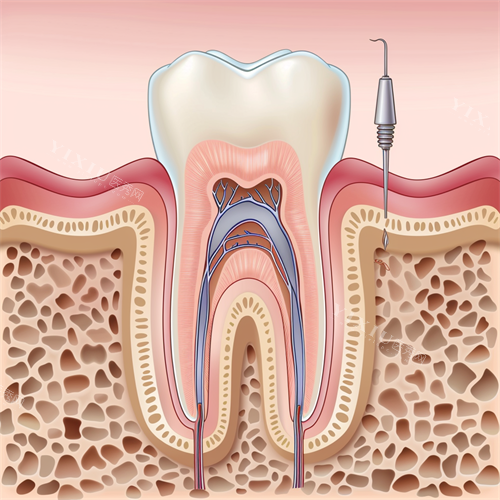

补牙费用:树脂补牙价格在198-350元起

具体取决于龋齿大小和补牙材料。驰康口腔采用的进口树脂材料补牙,价格可能在220-300元区间,性价比较高。